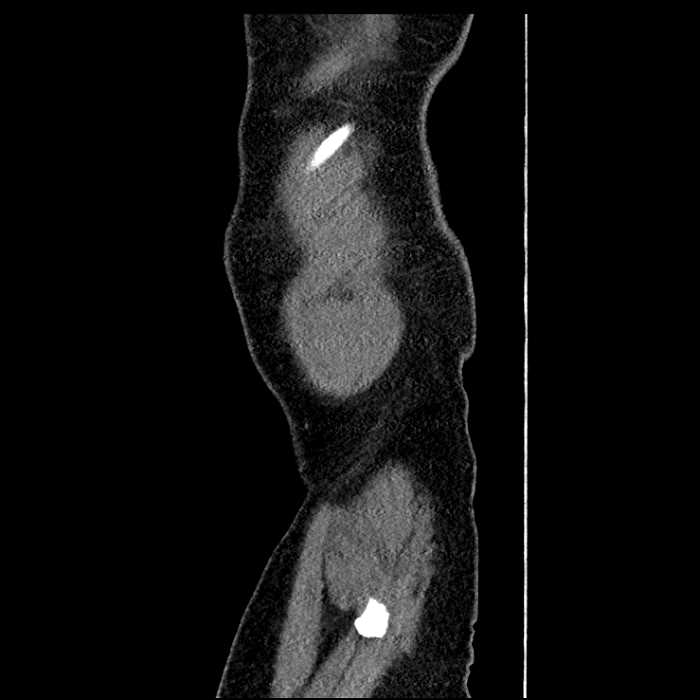

• Large fluid density structure in hepatic segments 7 and 8 measuring 10 x 7 x 7 cm with internal septation and circumferential ill-defined low density compatible with edema

• Peripherally enhancing subcapsular collections along the anterior margin of the left hepatic lobe measuring 3 x 1 cm and 2 x 1 cm

• Clearly marginated fluid density structure in segment 7 and several other scattered tiny hypodensities, which likely represent cysts

• The classic CT imaging appearance is a double target sign with internal low density surrounded by an internal enhancing rim (capsule) and a low density external rim (edema)

• Abscesses may be unilocular or multilocular

• Gas is present in a minority of cases

Hepatic abscess showing the double target sign with low density internally surrounded by a thin inner enhancing rim (red arrow) and ill-defined outer low density rim (yellow arrow). Blue arrow indicates an internal septation. Red arrows: additional smaller subcapsular abscesses. Red arrow: focal contained perforation associated with diverticulitis.